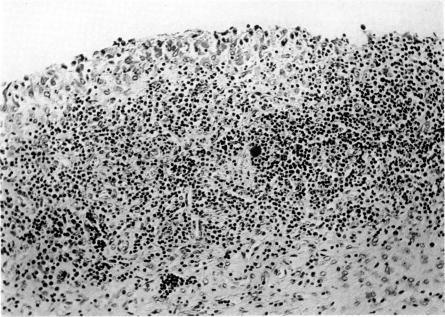

Eight-week-old pigs fed a protein-rich diet developed an abnormal intestinal microbial flora within 1 week. The main feature was a significant increase in the number of atypical , type A. In the first week after the change of diet, the pigs showed disturbances of movement and swollen peripheral joints. The ESR was concomitantly elevated and later on hypergammaglobulinaemia with increased antibody titres to antigens were noted. Joint deformities were observed after some months. The joint lesions consisted of synovitis with a cell-rich exudate. The lesions of the synovial tissue were characterized by proliferation of the synovial lining cells with villous hypertrophy and highly vascularized granulation tissue containing accumulations of lymphoid cells. Pannus formation and erosion of joint cartilage were seen in some animals. Bacteriological examination, including search for mycoplasmas, was negative. Subcutaneous nodules of rheumatoid nature were also found. Signs of proliferative glomerulonephritis were demonstrated in most of the animals. Different pathogenic aspects are discussed with regard to the direct influence of antigens on the joint tissues, circulating antigen–antibody complexes and cell-bound antibodies. As the same abnormal intestinal flora and immunological reaction to intestinal have been found in human rheumatoid disease, this diet-induced pig arthritis of remarkably similar clinical and histological characteristics is of special interest.

八周龄的猪喂食富含蛋白质的日粮后,在1周内肠道微生物群就出现异常。主要特征是A型非典型菌数量显著增加。在日粮改变后的第一周,猪出现运动障碍和外周关节肿胀。同时血沉升高,随后出现高球蛋白血症,抗体对抗原的滴度增加。几个月后观察到关节畸形。关节病变包括伴有富含细胞渗出液的滑膜炎。滑膜组织病变的特征是滑膜衬里细胞增殖、绒毛肥大以及含有淋巴细胞聚集的高度血管化肉芽组织。在一些动物中可见血管翳形成和关节软骨侵蚀。包括支原体检测在内的细菌学检查均为阴性。还发现了类风湿性质的皮下结节。大多数动物显示出增殖性肾小球肾炎的迹象。就抗原对关节组织的直接影响、循环抗原 - 抗体复合物和细胞结合抗体等方面讨论了不同的致病因素。由于在人类类风湿疾病中也发现了相同的异常肠道菌群和对肠道的免疫反应,这种饮食诱导的猪关节炎在临床和组织学特征上与人类非常相似,具有特殊的研究意义。